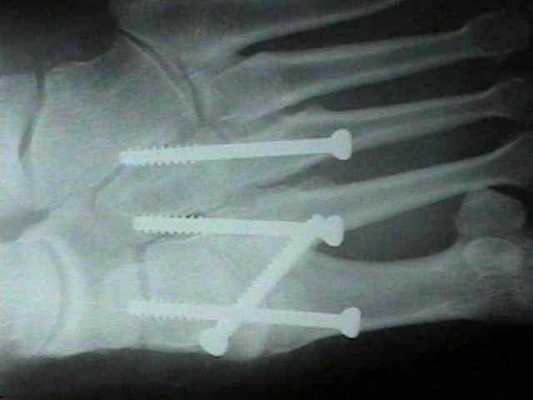

При смещении более 2 мм, нестабильности при функциональных тестах – рекомендовано открытое устранение вывиха с жёсткой фиксацией винтами или пластинами. Используются один или два продольных доступа в 1 и 2 межплюсневых промежутках. После обнажения первого предплюсне-плюсневого сустава первым этапом устраняется межклиновидная нестабильность, вторым этапом устраняется предплюсне-плюсневая нестабильность. В послеоперационном периоде сразу начинается разработка активного объёма движений. Нагрузку на стопу начинают постепенно, с тем чтобы полностью её восстановить к 6-8 неделе. Удаление спиц Киршнера производится через 6-8 недель, компрессирующих винтов через 3-6 месяцев. Возвращение к полной физической активности не ранее 9-12 месяцев после операции.

Открытое вправление вывиха, трансартикулярная фиксация 1-2-3 предплюсне-плюсневых суставов винтами.